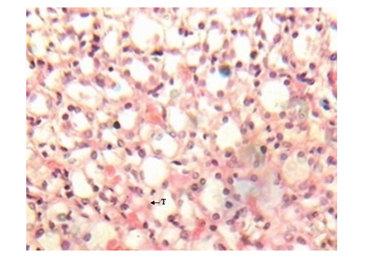

Figure 7 Kidney micrograph of control rat showing normal tubular(T) structures at 3 and 5 weeks. (H & E stain X400).

Figure 8 Kidney micrograph of diabetic rat showing mild tubular damage(T) at 3 weeks. (H & E stain X400).